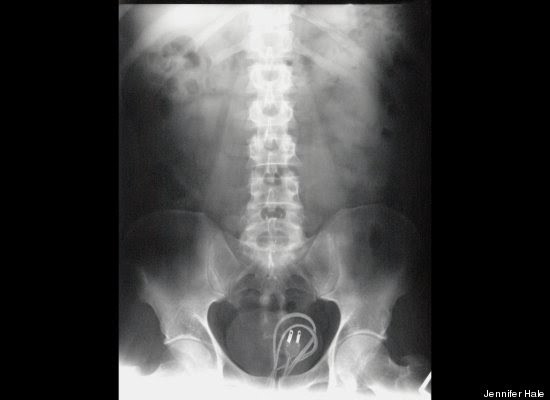

"Stack Up!" es una muy divertida colección de 100 imágenes de rayos X que muestra cuerpos extraños ingeridos o insertados en el cuerpo humano, tanto por accidente o de forma voluntaria, aunque se haga difícil imaginar el motivo de algunas de tales inserciones.

Redactado de manera humorística, el libro se pregunta cómo un teléfono celular puede haber ido a parar al sitio de la anatomía del propietario donde nunca da el sol, respondiéndose que, probablemente, estuviera en modo vibrador.

"Hallar un termómetro atascado en el recto de un adulto puede resultar corriente. Pero ¿Qué se puede decir de una muñeca Barbie, perteneciente a su hija de seis años?", se preguntan los autores, añadiendo el consejo infaltable: no hagan esto en casa.